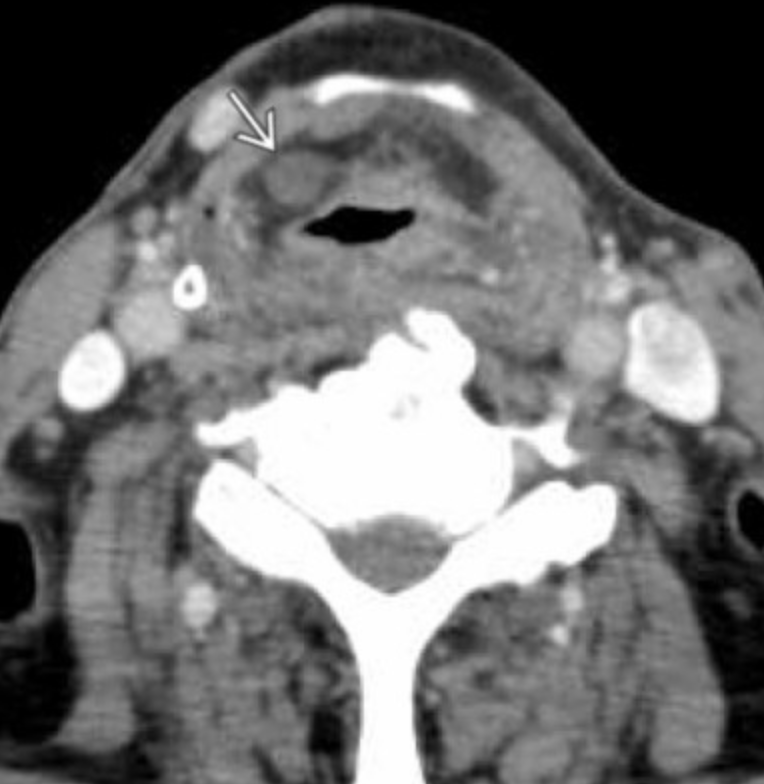

• Hypervascular mass in carotid space which splays the internal and external carotid arteries

• Early washout

• May have salt/pepper on MR

• Salt = increased signal from hemorrhages (not a common finding)

• Pepper = flow voids from vascularity - serpentine or punctate flow voids

• Hypoechoic and vascular on US

• Unilateral, may be bilateral in inherited syndromes